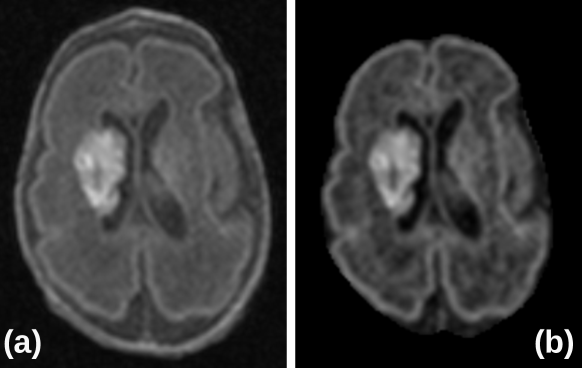

The dataset obtained from Hospital Universitario Puerta del Mar (HUPM) originates from clinical settings, involving preterm neonates who may present with neurological abnormalities, such as abnormal tissue structures or atypical brain morphology (Figure 8). Some of these patients have been incorporated into the training dataset, while others are allocated to the test dataset to evaluate the model’s generalizability and robustness. Despite the inherent challenges associated with these variations, the results demonstrate that the performance of the proposed method on the test dataset is superior to that of conventional methods. This indicates that the proposed method can be effectively accommodated and adjusted for clinical abnormalities in its analyses. We attribute this robustness to the network architecture, which enhances its ability to generalize across uncommon and variant anatomical features.

Figure 8: a) Axial section of a 3D MRI from the HUPM dataset, showing the brain at 29 weeks of postmenstrual age (PMA). This image showcases typical neuroanatomical features and potential abnormalities often found in preterm neonates, providing a baseline for preprocessing assessment. b) The same image post-application of the MGA-Net, demonstrate the effectiveness of the network in enhancing image clarity and detail for better clinical assessment.